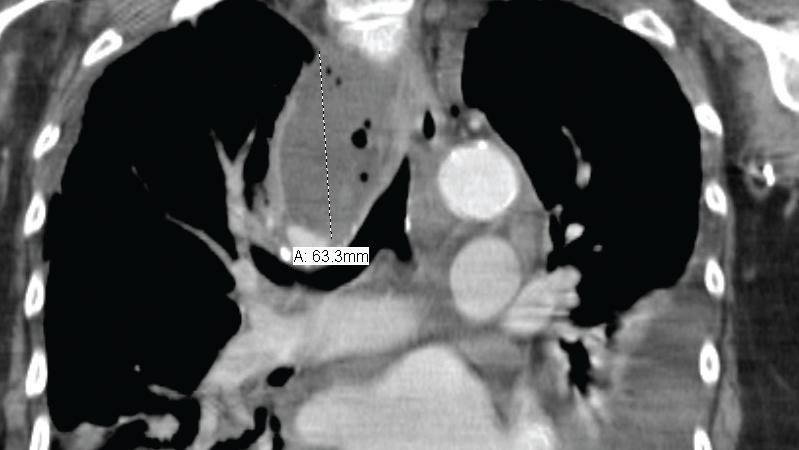

Figure 4 - ACT scan of the chest (coronal view) obtained November 9, 2005, shows extensivebilateral subcutaneous emphysema involving the base of the neck and extending into the deepcervical regions. Diffuse pneumomediastinum is also present without evidence of pneumothorax.Mild epicardial fat stranding is noted, consistent with inflammatory changes around thepericardium.